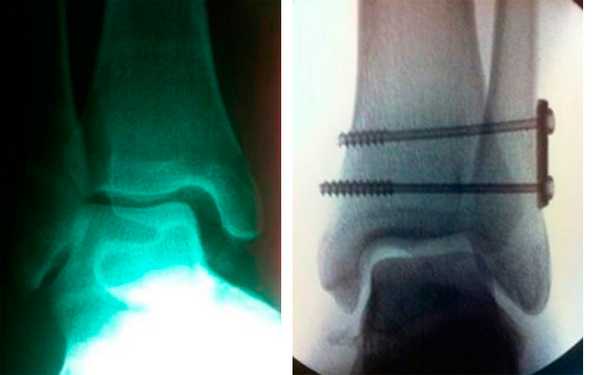

![]() | ![]() |

| Рис. 4. Разрыв межберцового синдесмоза, увеличено расстояние между большеберцовой и малоберцовой костями | Рис. 5. Разрыв передне-нижней связки синдесмоза на магнитно-резонансной томограмме |

Хирургическую операцию делают при разрыве предней и задней связок межберцового синдесмоза, разрыве связок с расхождением берцовых костей более 2 мм, разрыве связок с нарушением функции голеностопного сустава. При остром повреждении синдесмоза, который дает нестабильность, делают операцию, в ходе которой репонируют малоберцовую кость в вырезку большеберцовой и фиксируют кости винтом. При разрыве синдесмоза в сочетании с переломом берцовых костей и переломо-вывихом голеностопного сустава делают остеосинтез обеих берцовых костей и фиксацию синдесмоза путем стяжки вилки голеностопного сустава. При хронической нестабильности, вызванной разрывом синдесмоза, делают такие операции, как реконструкция передней, задней и межкостной связок синдесмоза, тенодез короткой малоберцовой мышцы, аутопластику трансплантатом из сухожилия длинной малоберцовой мышцы, аллопластику с помощью синтетических связок. После вмешательства накладывают гипсовую иммобилизацию. Для восстановления целостности синдесмоза делают операцию фиксацию межберцового синдесмоза винтами или стягивают берцовые кости с помощью связки. Кости временно свинчивают с помощью компрессионного винта на 6 недель. Нога находится в гипсовой повязке в течение 3 недель. После снятия гипса на ногу надевают ортез или тутор. Тутор ограничивает движения стопы в сагиттальной плоскости и оказывает компрессионное воздействие на лодыжки. Благодаря давлению на берцовые кости с двух сторон поддерживается необходимое расстояние между ними, что способствует срастанию связок синдесмоза.